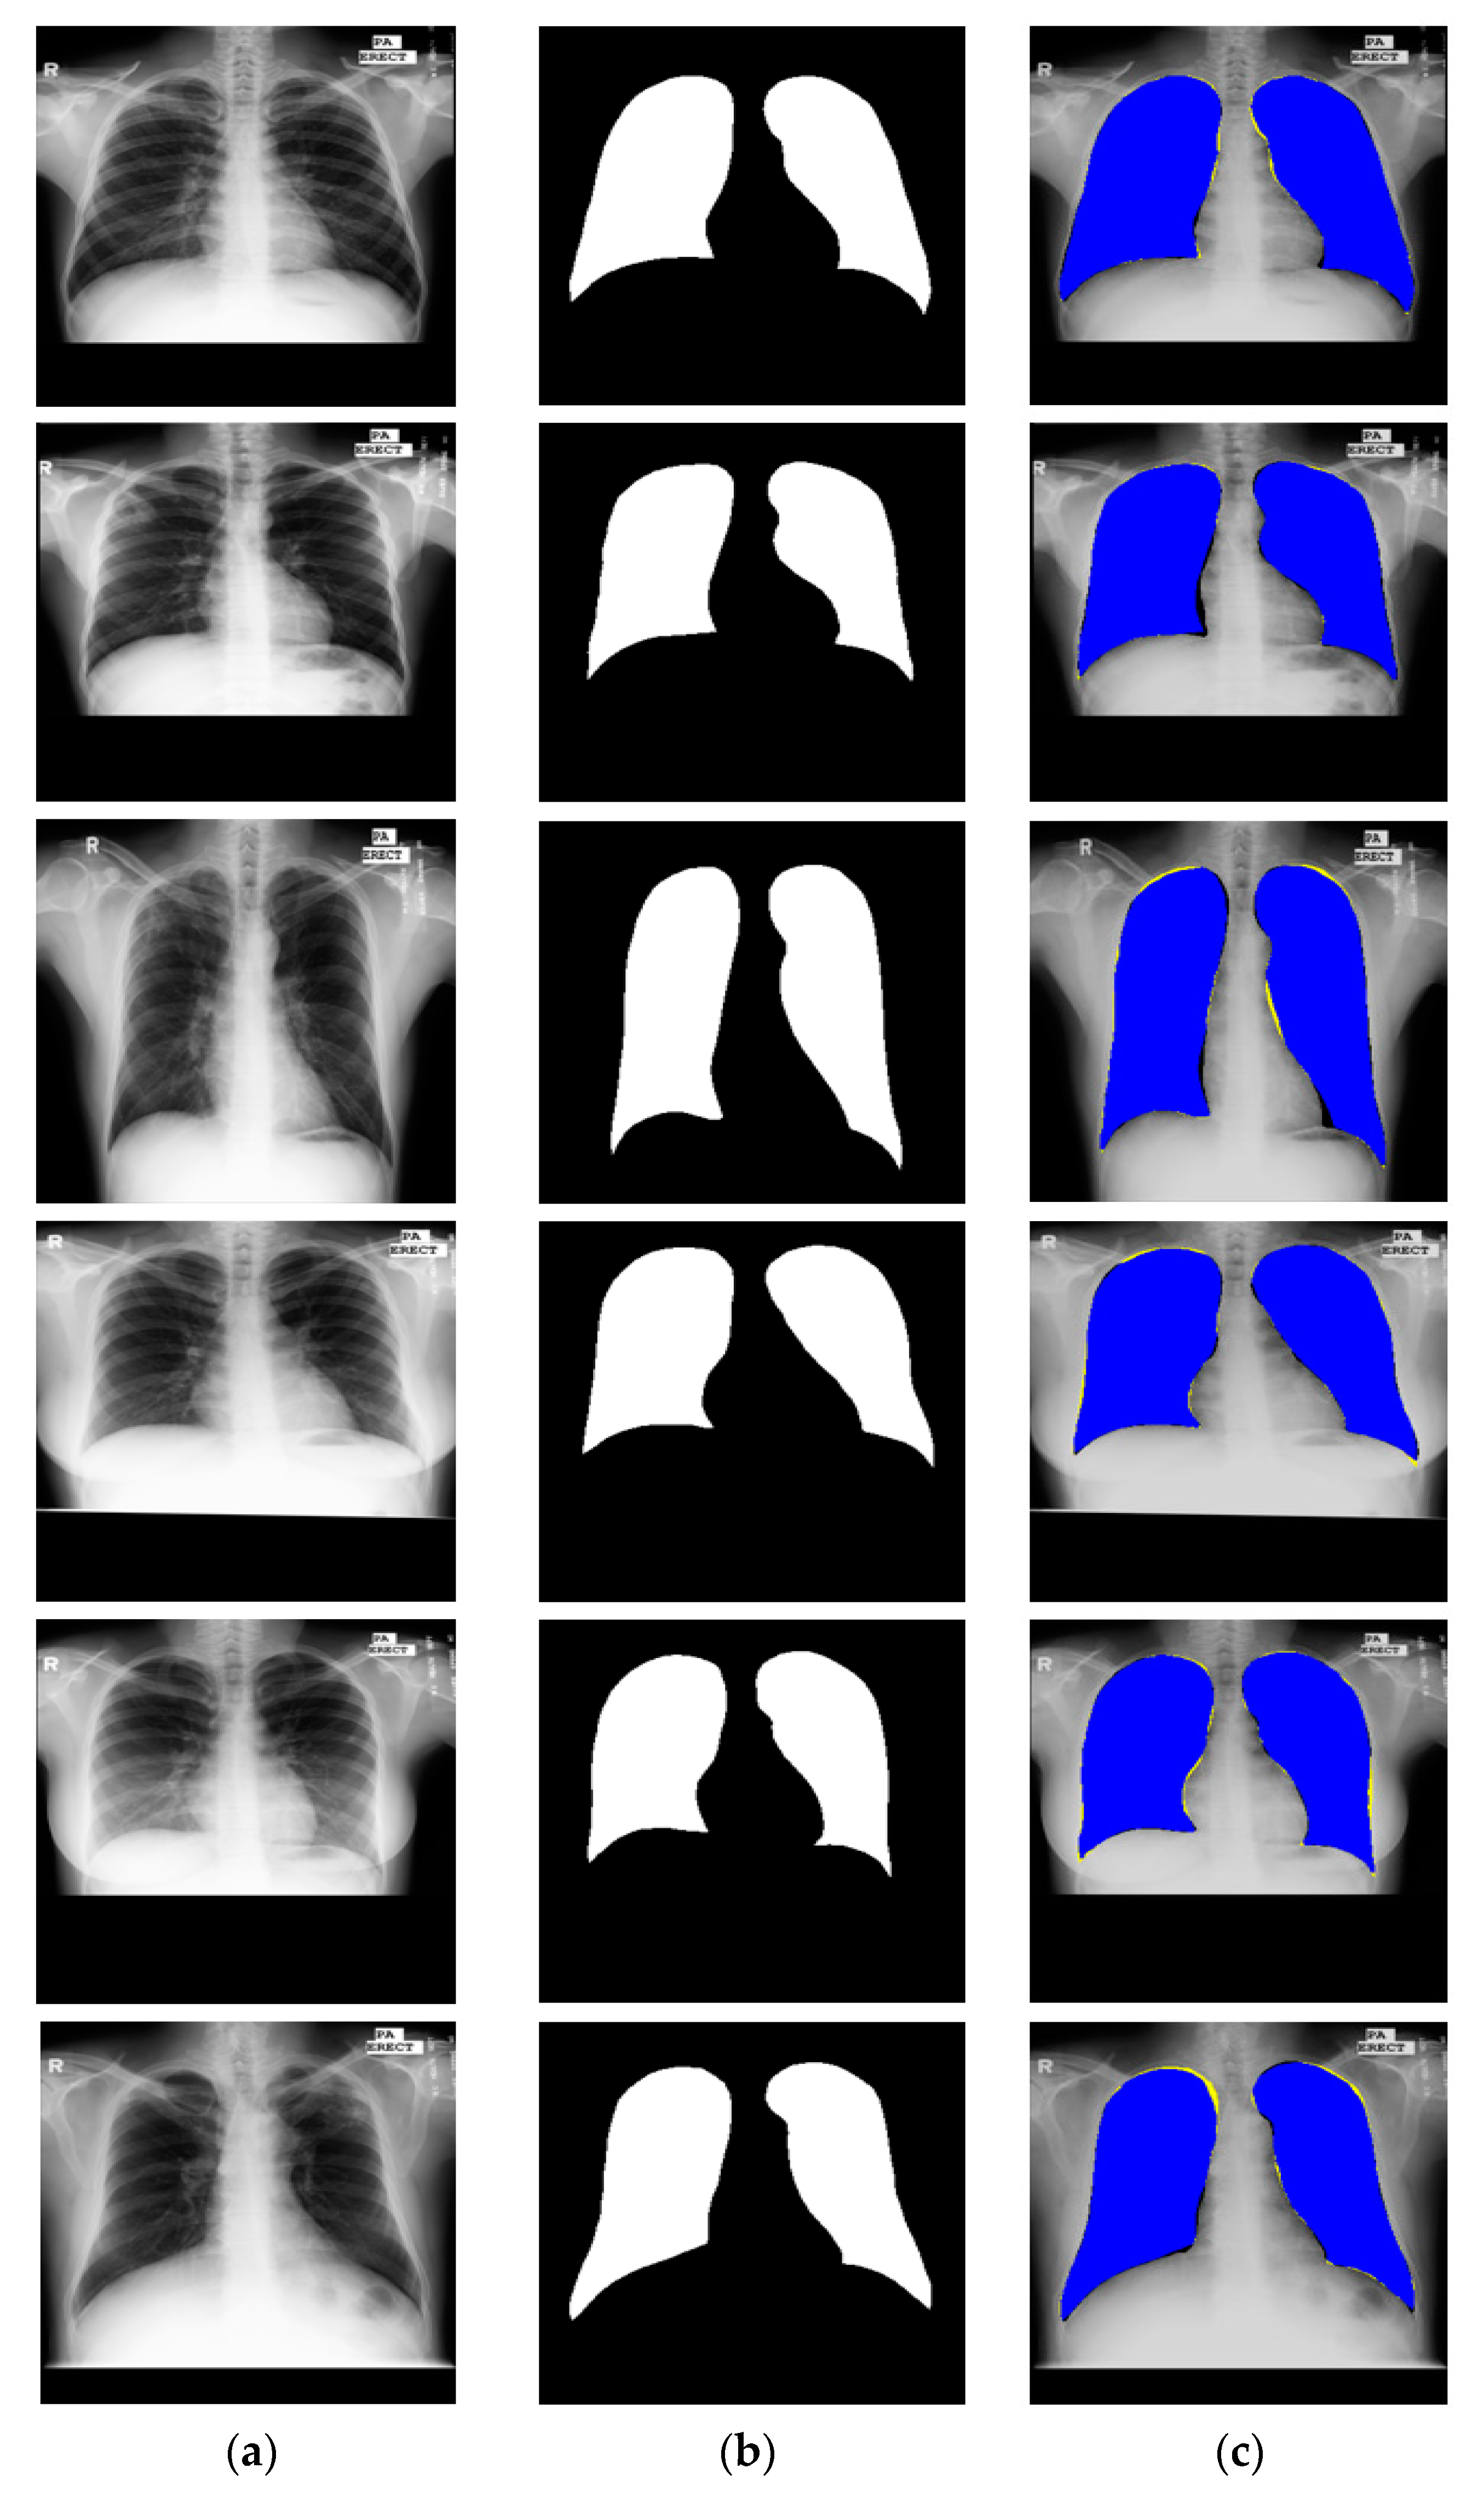

3.4.1. X-RayNet Testing for Chest Anatomy Segmentation

3.4.2. Chest Organ Segmentation Results by X-RayNet